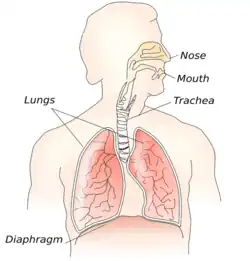

Foreign body aspiration

| Foreign body aspiration | |

|---|---|

.jpg) | |

| Aspiration of corn kernel that became lodged in the airway of an adult patient. | |

| Specialty | Respirology |

| Symptoms | Fever, choking, sore throat, drooling, stridor, speech difficulties, cyanosis, bronchitis, coughing, wheezing |

| Complications | Pulmonary aspiration, blockage, pneumonia, respiratory failure, respiratory infection, cardiopulmonary arrest, pulmonary embolism, pulmonary hemorrhage |

| Usual onset | Sudden or gradual |

| Risk factors | Children ages 3 and lower, alcoholism, drug abuse, senility, Parkinson's disease, improper eating habits, chest trauma, neck trauma, Alzheimer's disease |

| Differential diagnosis | Asthma, COPD, lung cancer, poisoning, drug overdose, cyanide poisoning, epileptic seizures, esophageal cancer, laryngeal cancer |